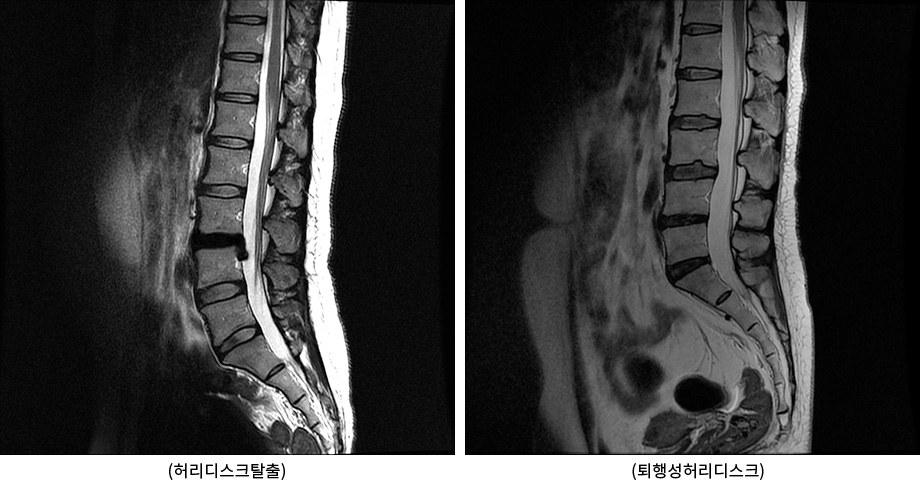

척추와 뼈 사이에 위치한 이 디스크는 외부로부터의 물리적 충격을 완화하고 단단한 뼈가 직접 충돌할 때 문제가 발생하지 않도록 하는 탄성이 높은 구조입니다. 외부의 영향이나 잘못된 위치로 인해 디스크가 꺼지면 염증이 발생하고 신경이 눌려 요통과 요통이 발생합니다. 기술적으로는 요추 디스크 분리라고 하며 일반적으로 요추 디스크 고장이라고 합니다.

허리디스크는 갑작스러운 질병이 아니다.

디스크는 몸이 척추로부터 떨어져 많은 고통을 느낄 때까지 여러 단계를 거칩니다.